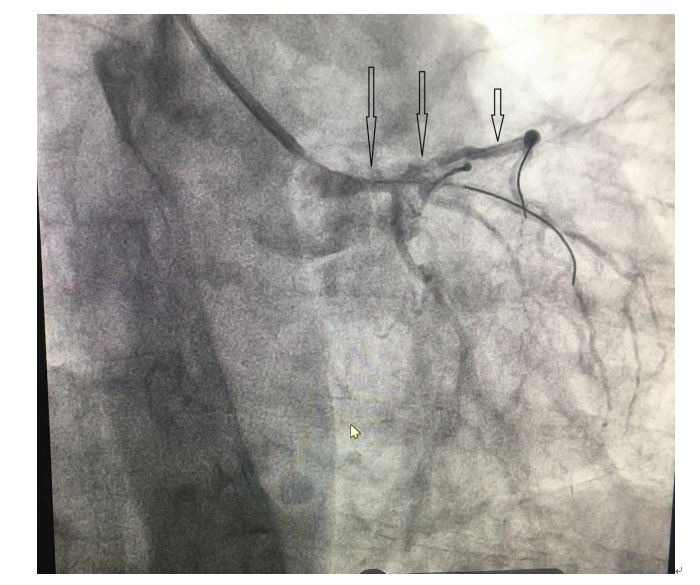

根据造影结果看,病变非常严重,介入处理累及左主干和前三叉的病变属于非常高危的操作,建议首选外科开胸处理。但胡大爷不想去外科搭桥,信任我们,愿意做冠脉介入治疗。郑全副主任医师、龙泉杉主治医师、梁婷主管护师,用三枚支架撑起了关键点,圆满完成手术。

(三)支架植入

(四)支架植入后效果